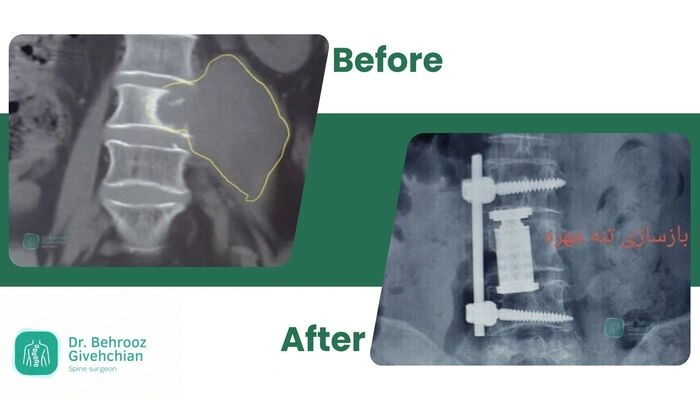

۴. جراحی ترکیبی

در شکستگیهای پیچیده یا همراه با متاستاز وسیع، ترکیبی از روشهای فوق به کار میرود.

- ابتدا توده یا بخش فشرده کننده نخاع برداشته میشود.

- سپس مهره آسیب دیده بازسازی و ستون فقرات با پیچ و میله تثبیت میگردد.

✅ مزیت: درمان همزمان علت فشار بر نخاع و ناپایداری ستون فقرات، و بهبود کیفیت زندگی بیمار